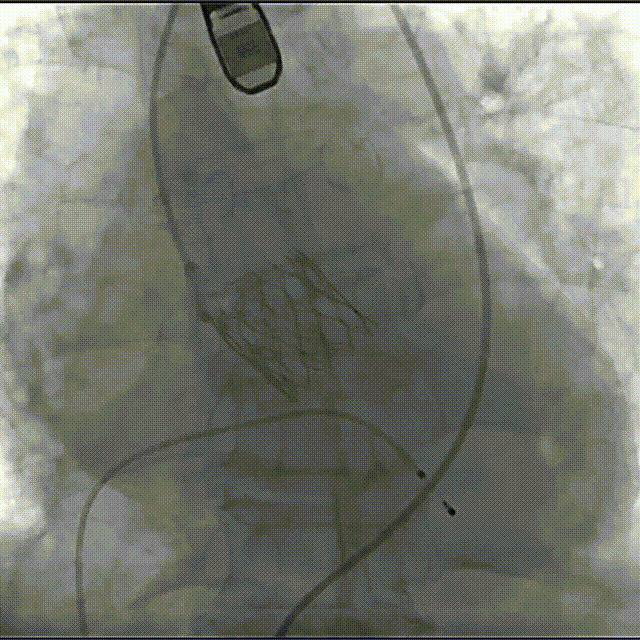

瓣膜0位定位释放

瓣膜稳定释放至全展开,无明显下滑,位置稳定

造影评估,瓣膜位于瓣下2mm形态稳定

左冠切线评估,小弯侧深度6mm

无张力脱钩,瓣膜无位移

最终造影,无瓣周漏